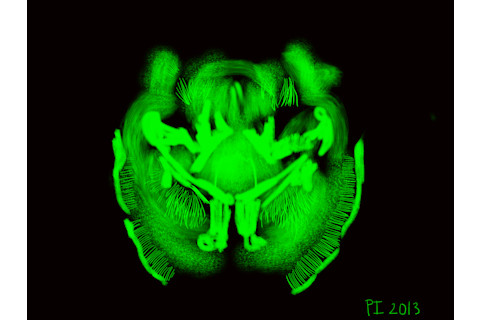

斯坦福大学的研究人员上周首次展示了他们将整个大脑器官透明化的新技术,在神经解剖学和“连接组学”领域引起了轰动。

这项技术预示着研究人员能够轻松地从各个层面——从大型神经元网络到深埋在大脑中的结构——观察大脑的新时代。通常阻碍研究人员观察大脑的是脂质的存在,

它们是脂肪细胞,阻碍光的通过,并且不被化学物质渗透。另一个脂质难题是它们具有结构性:它们有助于形成细胞膜。通常,当脂质被去除时,组织就会散开。一个变成一堆果冻的透明大脑对研究没有什么用处。由卡尔·戴塞尔罗斯及其团队开发的CLARITY技术,第一作者Kwanghun Chun说,它可以“将生物组织转变为一种新状态”,

这是一项重要的科学方法学进展。基本上,它使用水凝胶从内部石化大脑。将完整的死后大脑浸入水凝胶溶液中,一种称为单体的小分子

会渗透到组织中。然后将大脑加热到体温左右,单体结合形成聚合物网格,将大脑中的所有物质固定在一起,但不结合脂质——就像大脑的水凝胶发网一样。研究人员随后迅速去除脂质,露出一个透明且保存完好的大脑。

这种水凝胶-大脑混合体比未经处理的组织更坚硬、更稳定。它可以用于将脆弱和罕见的疾病标本转化为可重复使用的资源,从而发挥类似大脑借阅图书馆的作用。同样重要的是,科学家可以利用这项技术对大脑进行可重复的分子研究。研究人员可以为一项研究对感兴趣的细胞群和神经元进行荧光染色,然后将水凝胶大脑清洗干净,再为另一项研究染色不同的细胞群。

希望是,能够看到整个大脑全貌

——从鸟瞰到微观角度——可以帮助科学家理解大脑的变化如何导致疾病。《自然》杂志关于透明大脑的视频:http://www.youtube.com/watch?v=c-NMfp13Uug&feature=youtu.be